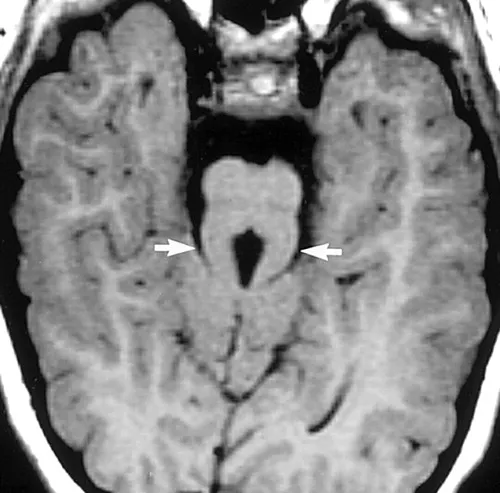

主な特徴は「臼歯徴候」と呼ばれる、脳の異常を示す特徴です。この異常は、脳の後方部分にある特定の構造の異常発達に起因し、MRIで確認できます。この異常はMRIで見ると臼歯の形状に似ており、その名前の由来です。

※臼歯徴候(Molar Tooth Sign)は、ジュベール症候群(Joubert syndrome)など一部の神経疾患で見られる特徴的な脳の異常の一つです。この徴候は、脳のMRI画像において、特定の構造が臼歯の断面に似ていることを指します。

臼歯徴候は、主に脳の後方部分、具体的には小脳海綿体や脳幹などの構造の異常発達に起因します。この異常はMRIで視覚的に確認でき、臼歯の形状に似ていることからこの名前がつけられました。MRIで中脳と橋の境界部(峡部)を通る断面において見ます。